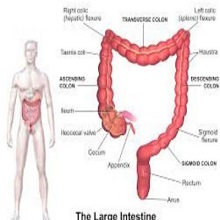

| Хемороиди или фиброваскуларни јастучићи аналног канала су део нормалне анатомске структуре и сматра се да су веома битни за одржавање континенције. Постоје два типа хемороида у односу на локализацију: спољашњи (у доњем делу аналног канала, испод зупчасте линије) и унутрашњи (у горњем делу аналног канала, изнад зупчасте линије). |

Апендицитис је упала слепог црева (апендикса). Слепо црево је узани део црева у облику црвуљка, дужине неколико центиметара. Једним крајем слепо црево везано је за почетни део дебелог црева, а други крај му се слепо завршава |

Исхемијски колитис је оштећење сегмената дебелог црева, које настаје као последица мезентеричне васкуларне оклузије. |

Дивертикулуми танког црева су локализована проширења цревног зида која су у вези са луменом црева. |

Појава крви у столици није нормална и не треба је игнорисати. Као што није нормално ни крврарење из носа тако није ни крв у столици, али се људи много раније јављају лекару због крварења из носа него због крварења из дебелог црева. Ово је, разумљиво, велика грешка. |